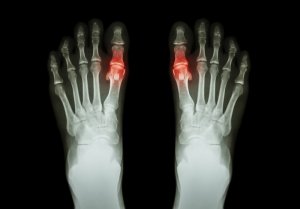

Kihdin oireet

Kihti voi aiheuttaa monia erilaisia oireita sen etenemisvaiheesta riippuen:

- Aluksi vain yksi tai useampi nivel kärsii kihdistä. Yleensä kyseessä ovat isovarvas, polvi tai nilkka. Tämä hyökkäys voi kestää vain muutaman päivän ajan, mutta se saattaa palata aina silloin tällöin.

- Yleisesti ottaen kipua ilmenee öisin, ja se on voimakasta ja sietämätöntä.

- Tyypillisesti kihdistä kärsivä nivel on punoittava ja kuuma, sillä se on tulehtunut. Yleensä se on myös arka ja turvonnut.

Toisaalta taas jotkut ihmiset saattavat kokea kroonista kihtiä. Se voi johtaa nivelten vahingoittumiseen ja liikkuvuuden vähenemiseen tietyissä nivelissä.